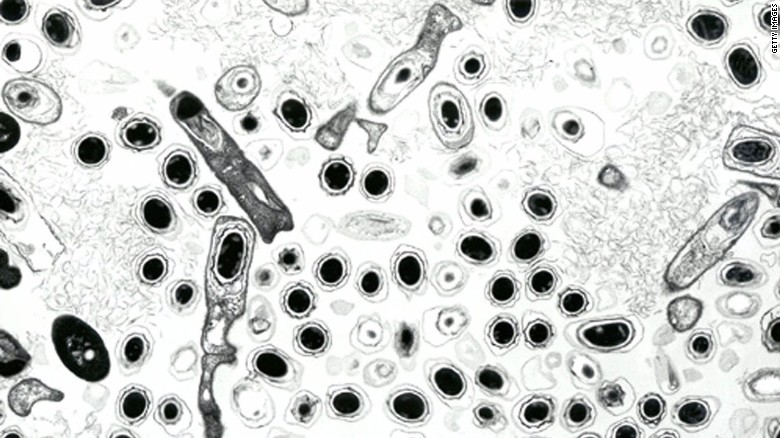

Anthrax is a potentially deadly bacterial disease caused by Bacillus anthracis, according to the World Health Organization. The hospitalizations came after up to 1,200 reindeer died over the past month, which officials originally blamed on a heat wave in the region. Unusually high temperatures of up to 35 degrees Celsius (95 degrees Fahrenheit) recorded over the past month might have weakened the reindeer. Now, laboratory tests have confirmed that the reindeer died of anthrax, Gov. Dmitry Kobylkin’s office reported.(CNN.COM/photo: Getty Images)…[+]